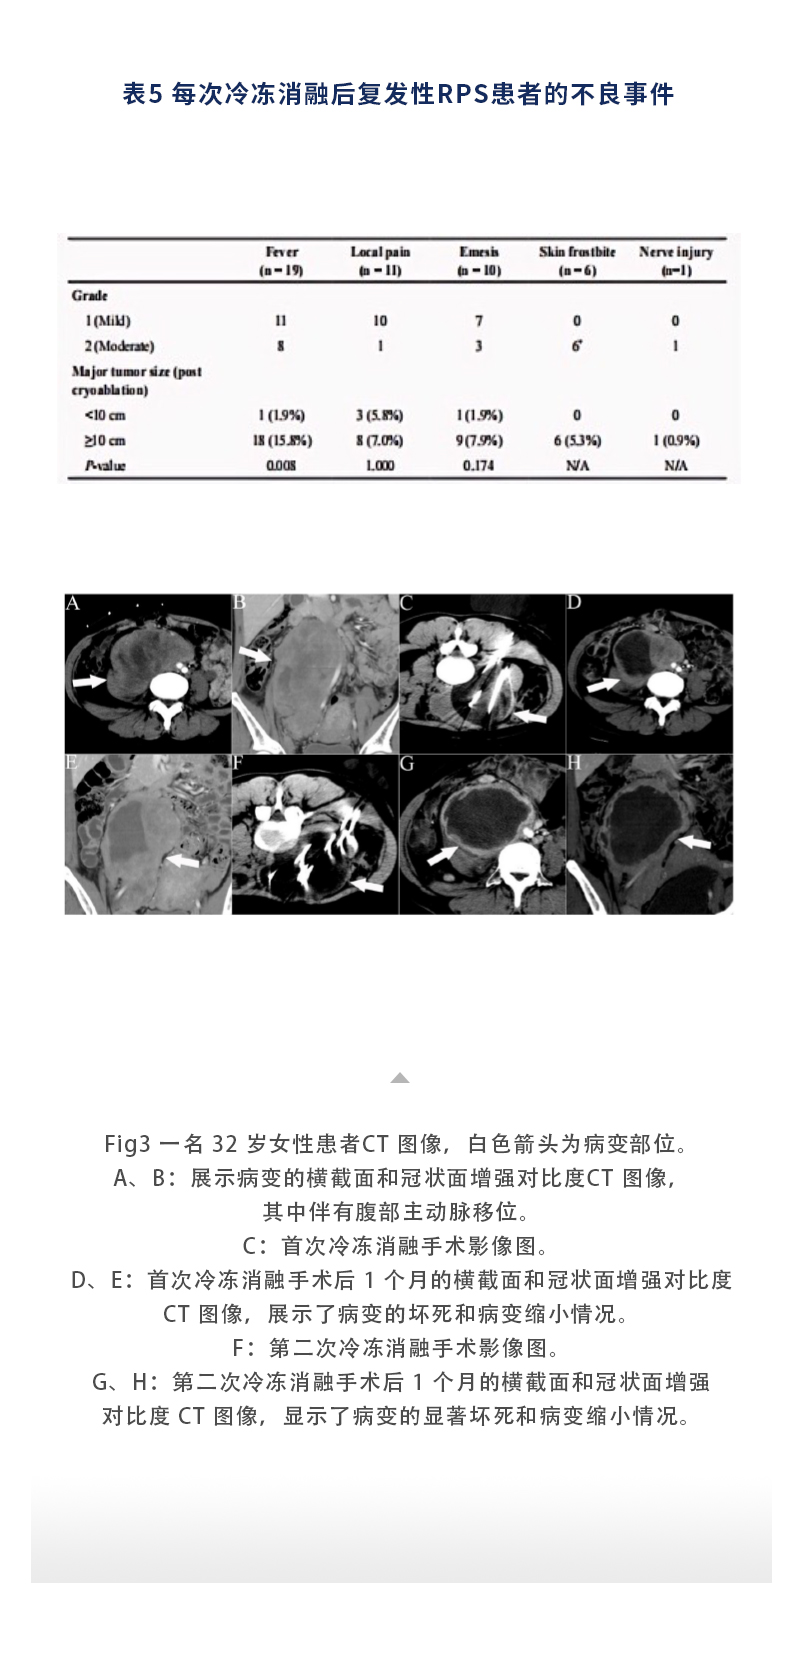

【HYGEA·科研資訊】軟組織肉瘤冷凍消融